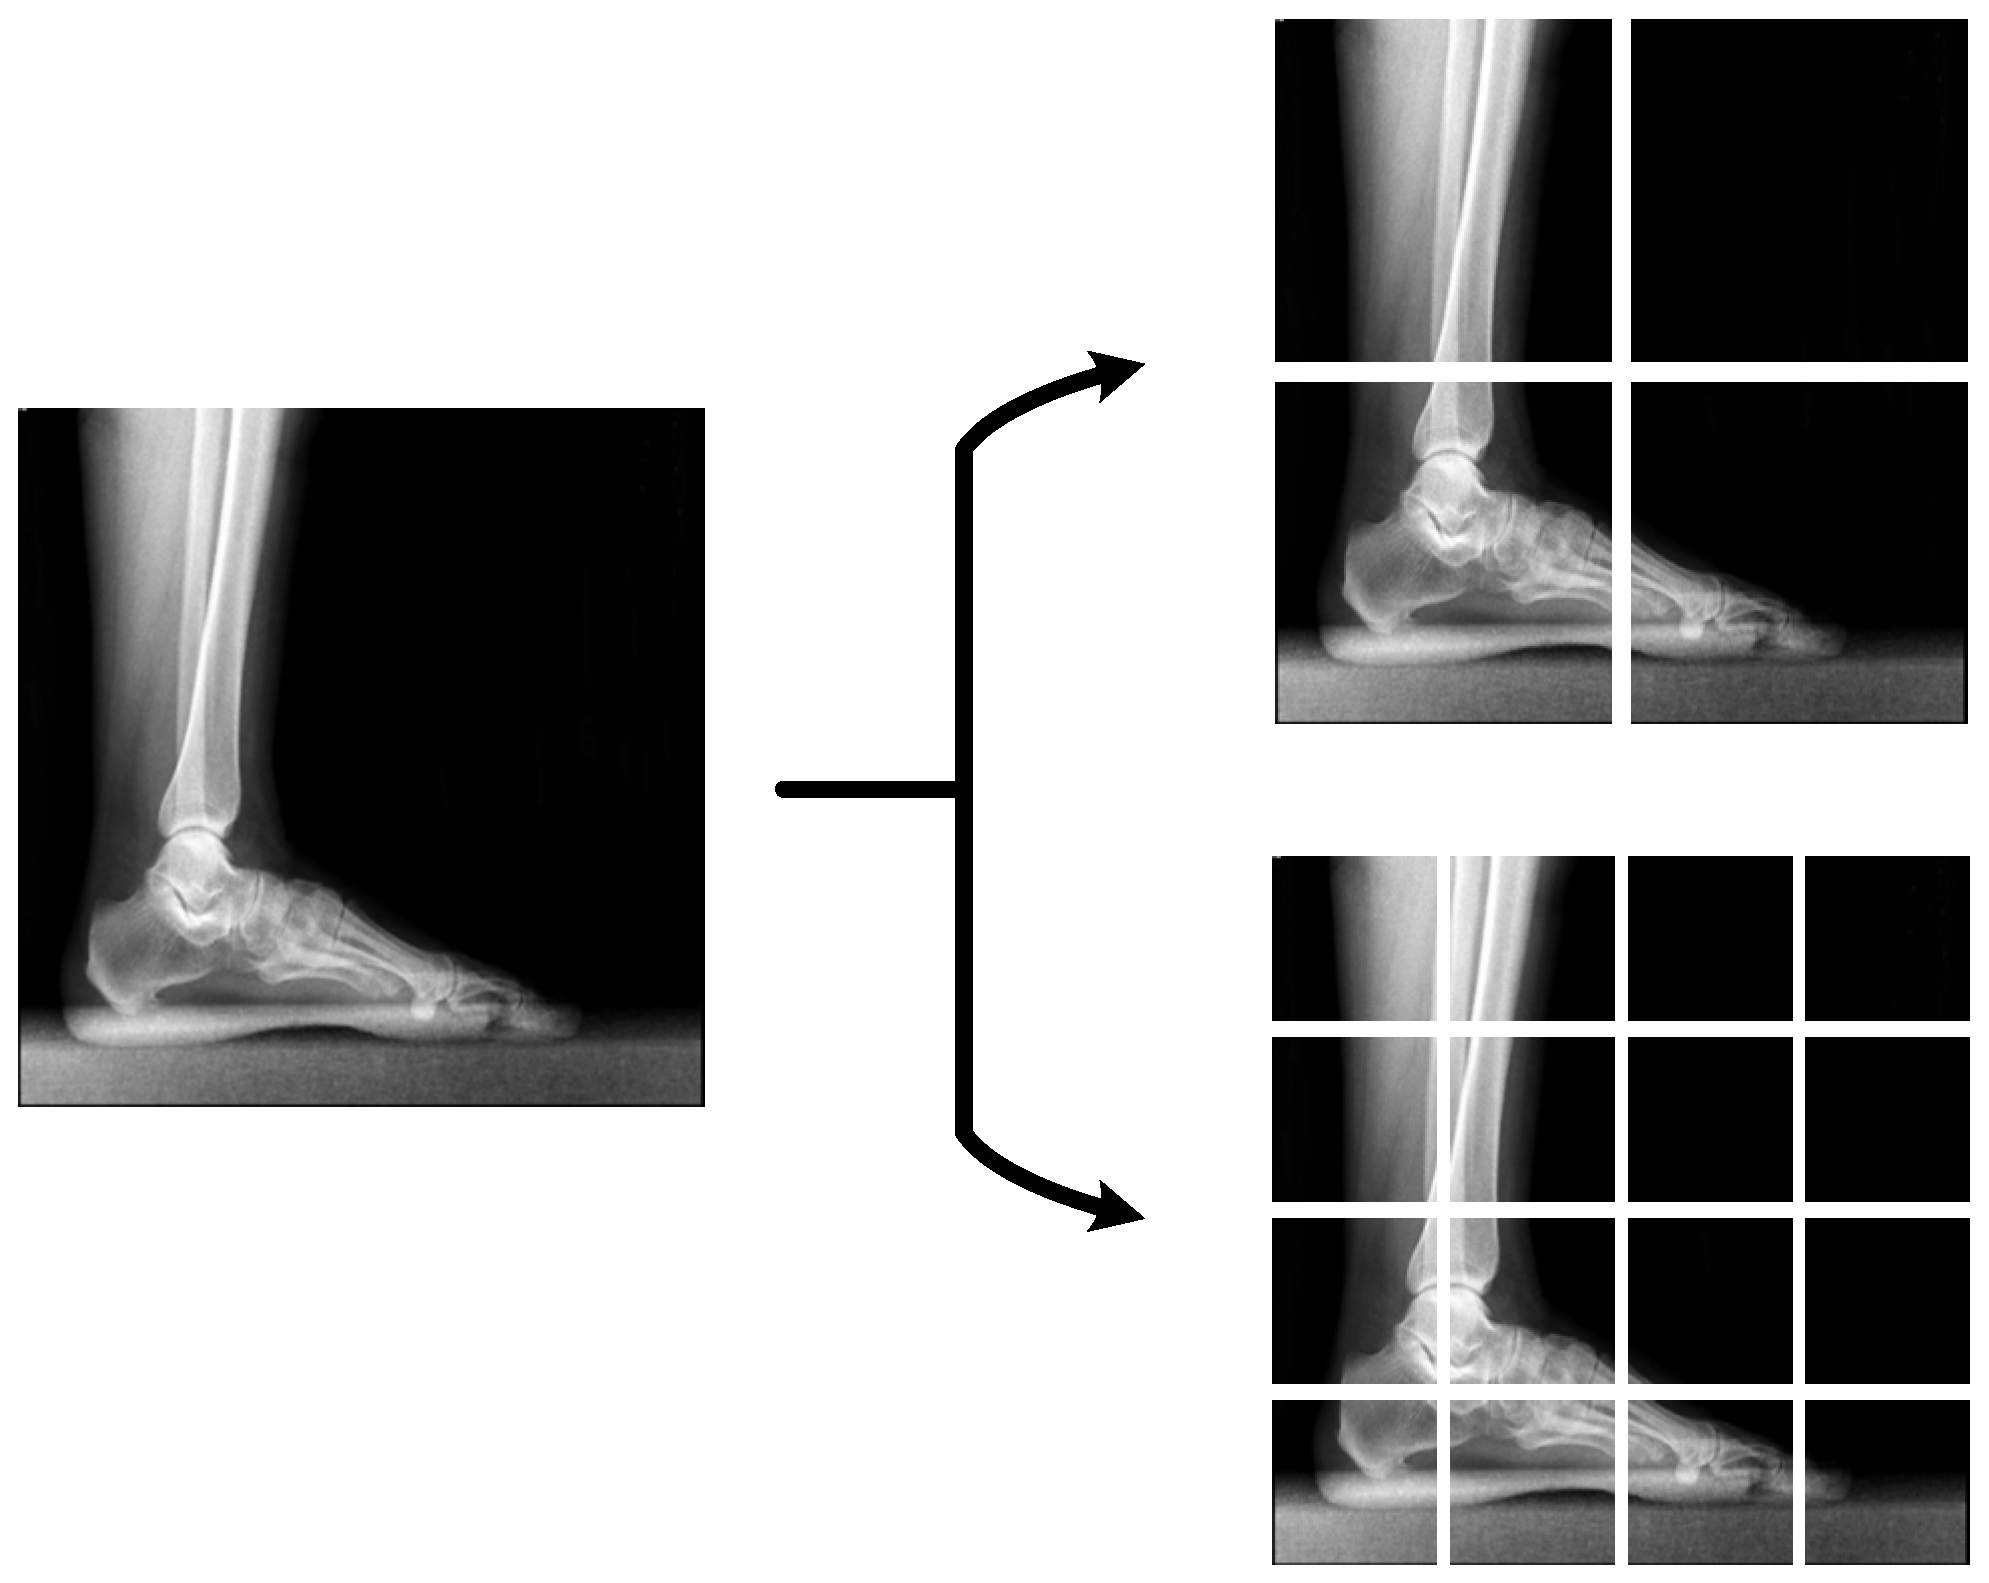

3.2. Preprocessing

| Input: Original X-ray image and 20 patches of original image. Output: 21,000-length feature vector extracted from popular pre-trained CNNs. for i = 1 to 21 alexfeats (1 + (1000 × (i − 1)):(i × 1000)) = alexnet(Xray_Imagei) mobilefeats (1 + (1000 × (i − 1)):(i × 1000)) = mobilenetv2(Xray_Imagei) densefeats (1 + (1000 × (i − 1)):(i × 1000)) = dense201(Xray_Imagei) googlefeats (1 + (1000 × (i − 1)):(i × 1000)) = googlenet(Xray_Imagei) vggfeats (1 + (1000 × (i − 1)):(i × 1000)) = vgg16(Xray_Imagei) resnetfeats (1 + (1000 × (i − 1)):(i × 1000)) = resnet50(Xray_Imagei) darknetfeats (1 + (1000 × (i − 1)):(i × 1000)) = darknet19(Xray_Imagei) squeezefeats (1 + (1000 × (i − 1)):(i × 1000)) = squeezenet(Xray_Imagei) end for |